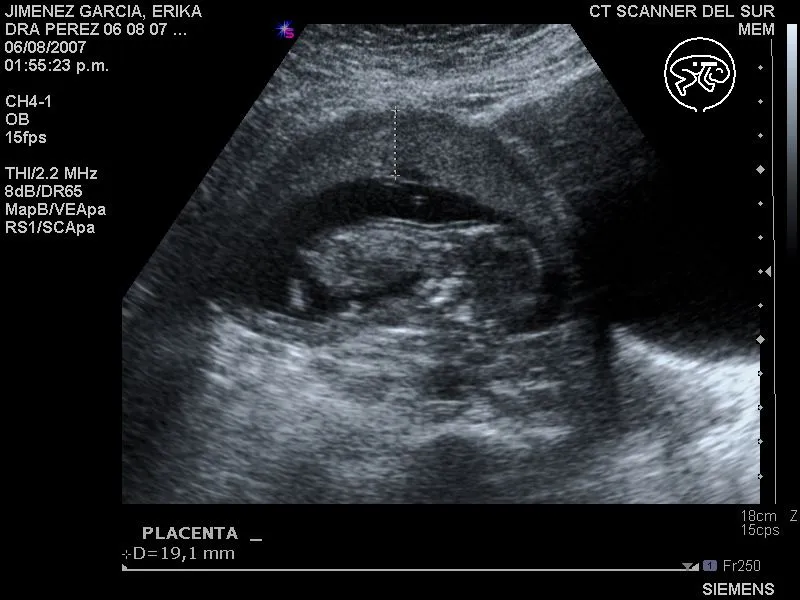

Ecografía de 1 mes de embarazo

Explora imágenes de ecografías de 1 mes de embarazo, ideales para entender las primeras etapas del desarrollo fetal y compartir la emoción.

Ecografías 2D - El Embarazo: todo lo que una embarazada debería saber

Indica el motivo para eliminar esta imagen: